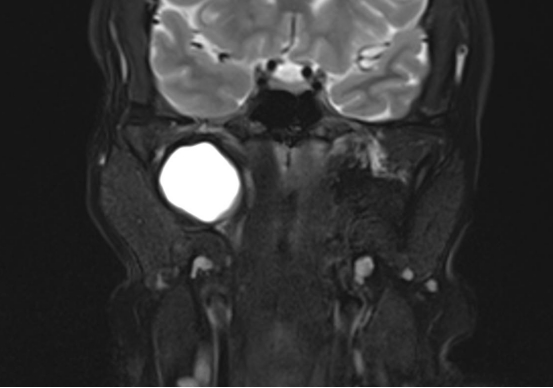

面对挑战,张继友副主任医师、魏巍主治医师、李鹏副主任医师、杨肖医师组成的手术团队迎难而上。术前,团队依托医院影像学平台完成了患者CT及MRI检查,对肿瘤的大小、性质、血供及其与周边重要血管神经的立体关系进行透彻评估,制定周详的手术方案和应急预案。

手术中,团队采用了经典的“经颈侧进路”。在有限的视野和操作空间内,手术团队凭借丰富的解剖知识和稳健的手术技巧,犹如一位技艺精湛的“拆弹专家”,在神经与血管交织的“密林”中小心翼翼地游离、显露,精准避开并保护颈内动脉、迷走神经、舌下神经等关键结构,最终将一枚直径约4cm的肿瘤完整、精准地剥离切除。整个手术过程出血量极少,所有重要神经功能均得到完美保留。术后患者恢复顺利,吞咽及发音功能良好,已康复出院。

1. 诊断:主要依靠影像学检查。增强CT或MRI(磁共振)是首选,能清晰显示肿瘤的位置、大小、边界及其与血管神经的关系,是制定手术方案的“导航图”,有时需要细针穿刺活检来明确肿瘤性质。